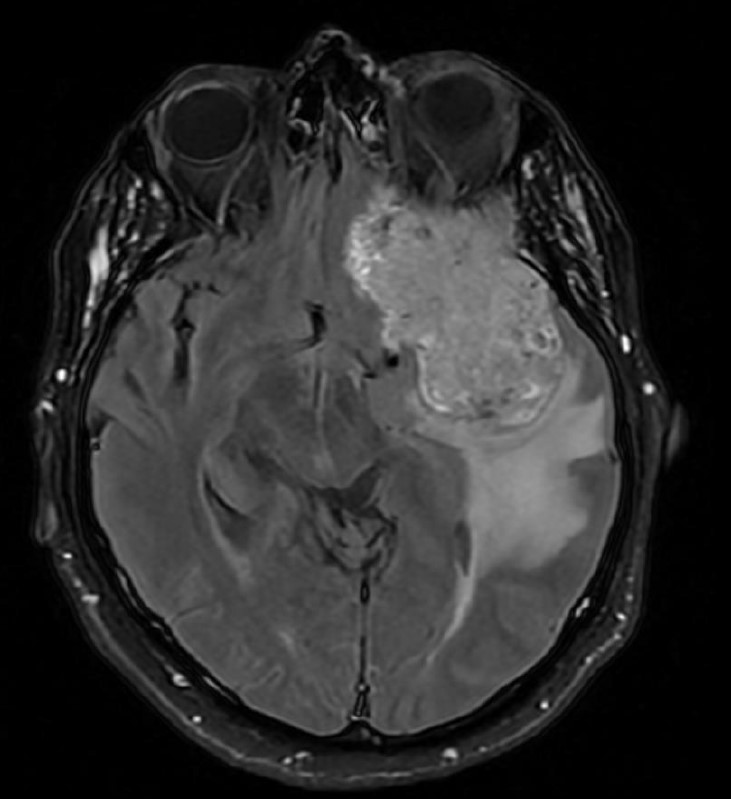

Unmasking cystic lesions